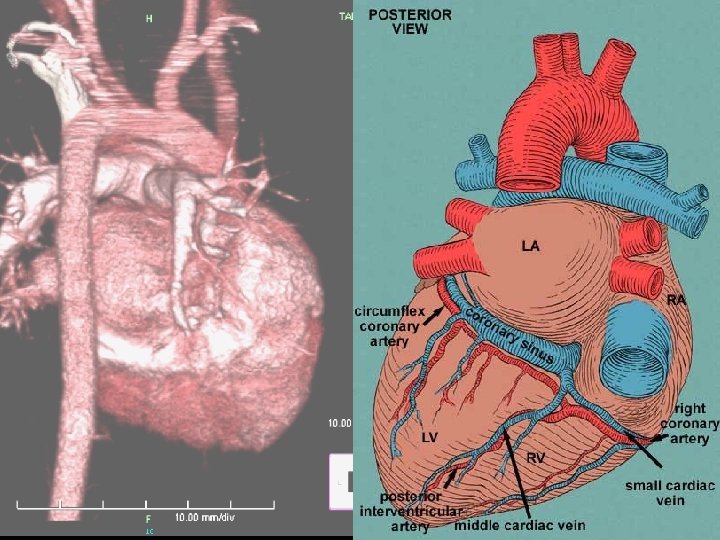

Hospital Course (6/25 -28) 3 D CT of chest performed on 6/25 n There is narrowing of the trachea in the level of aortic arch with narrowest diameter about 0. 25 cm about 1. 2 cm in length n There is dextrocardia with left side aortic arch n There is double SVC with left SVC drainage to coronary sinus n

Diagnosis identification of a right aortic arch on chest radiograph n An ill-defined arch location is often observed in patients with double aortic arch n compression of the trachea and hyperinflation and/or atelectasis of some of the lobes of either lung n chest radiography is not very sensitive n

n n barium esophagram to be the most important study Double aortic arch produces bilateral and posterior compressions of the esophagus

Diagnosis n n n Echocardiographic studies have been increasingly used for the diagnosis of a vascular ring Structures without a lumen, such as a ligamentum arteriosum or an atretic arch, have no blood flow and are difficult to identify identification of compressed midline structures and their relationship to encircling vascular anomalies may be difficult to detect

Diagnosis CT/MRI/Angio:These expensive radiological studies are rarely necessary to evaluate vascular rings n Although these modalities provide excellent delineation of all of the associated structures, they should be reserved for cases in which the results of barium esophagram do not provide a clear diagnosis n